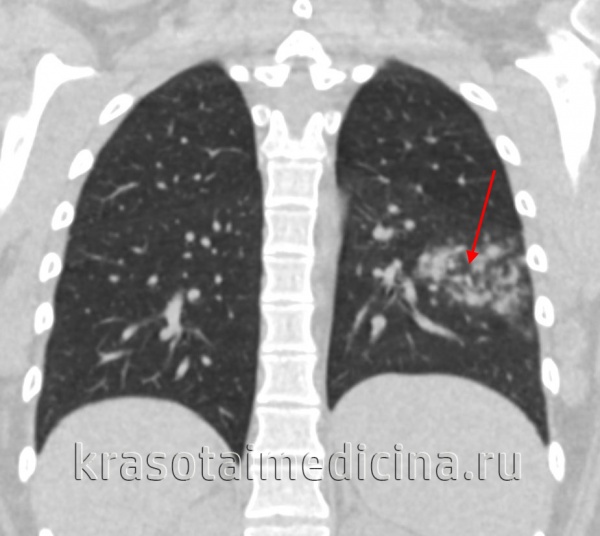

КТ ОГК. Ограниченная воспалительная инфильтрация легочной ткани в 6 сегменте нижней доли левого легкого.